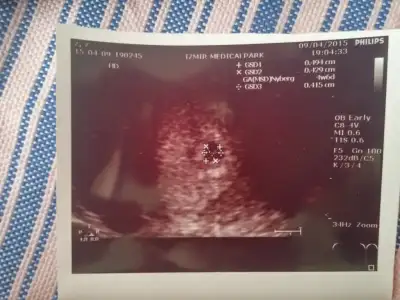

Kizlar benim kayinvaldem ogluna asik oglum oglum diye olen bi insan.. 1, 5yilda bana yaptigi oyunlarin haddi hesabi yok daha 1 aylik gelinken bende kalmaya basladi ben ise gidince esimin yaninda yatagimizda yatmalar neler neler... akla hayale sigmacak oyunlar yaslida degil cok genc 45 yasinda... esim icin hep susuyordum ben uzerime duseni yaptim en son kimyasal gebelik yasadigimda annanesini getirip 15 gun bana birakti. Artik esimide biktirdi. Benim giydigim kiyafetler gecelikler ic camasirlari ne alirsam bir hafta sonra aynisini aliyor benle yaris icinde surekli esime olmayan seyleri soyleyip aramizi bozmaya calisiyor. Ama cok sukurki esimle aramizdaki bag cok guclu. Birgun bile dediklerine inanmadi hep benim tarafimda oldu. Kiskanclik gozlerini kor etmis durumda bu yuzdende cocuk istemiyor. Hala ayirma cabasinda sen zayifsin cocugun olmaz sen soylesin sen boylesin. Artik rabbime havale ettim. Ben sabirla beni kabul edecegi gunu bekliyorum. Kafanizi sisirdim kusura bakmayin o yuzden kafam karmakarisik bisey yapar diye cok korkuyorum